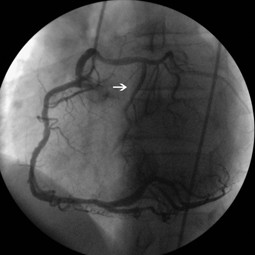

Fig. 1

Video 1. Right anterior oblique view shows that left main coronary artery originating from the proximity of the RCA and tracking an unusal direction to the left side and dividing into left anterior descending and left circumflex artery and LCx artery was totally occluded just after the division (avi 0,6MB)